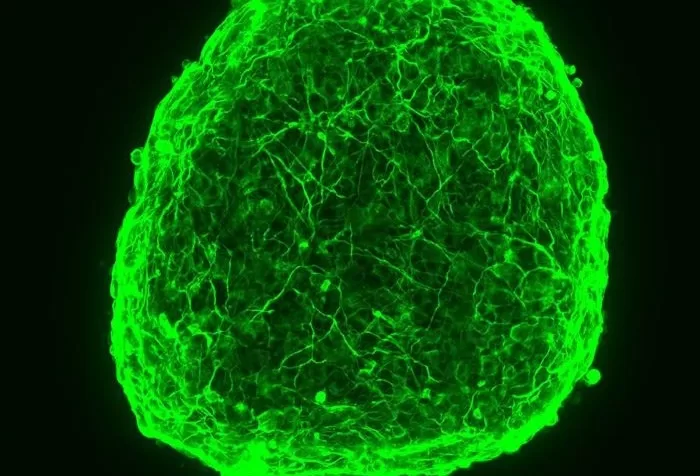

Neuroblastomas can be devastating to children and their families and the treatments can be harsh. But thanks to scientists, some tadpoles and a little poetry, improved...